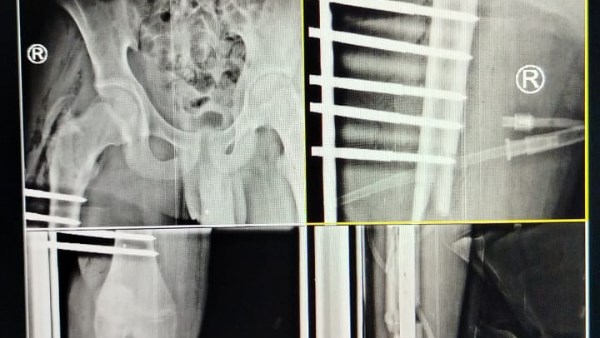

أكد الدكتور أحمد البيلي وكيل وزارة الصحة بالشرقية، أن الفريق الطبي بقسم جراحة العظام بمستشفى كفر صقر المركزي، بقيادة الدكتور محمد دومة أخصائي جراحة العظام، والدكتور أحمد إبراهيم أخصائي التخدير، وبمشاركة هيئة التمريض مي إبراهيم، وسعاد السيد، وفني الأشعة محمود محمد، نجح في إجراء جراحة ذات مهارة لشاب يبلغ من العمر ١٥ عاماً، أصيب بكسور مضاعفة مفتوحة بعظام الفخذ والقصبة بالطرف السفلي الأيسر، مع فقدان أجزاء من عظام الساق ونزيف حاد أدى إلى فقدان الوعي، وذلك نتيجة تعرضه لحادث سير.

واضاف محمود عبدالفتاح مدير الإعلام والعلاقات العامة بالمديرية، أن قسم الاستقبال والطوارئ بالمستشفى استقبل المريض في حالة حرجة، وتم التعامل الفوري بعمل الإسعافات الأولية وإيقاف النزيف وتثبيت الكسور بجبيرة، ثم نقله إلى العناية المركزة لتعويضه بالدم واستكمال كافة كافة الفحوصات اللازمة له، وبعد استقرار حالته، تم إدخاله غرفة العمليات لإجراء الجراحة، والتي شملت الرد المفتوح للكسور وتثبيتها باستخدام مثبت خارجي لعظام الفخذ، بالإضافة إلى تثبيت عظام القصبة بمسمار نخاعي تشابكي مع شرائح ومسامير، وتمت العملية بفضل الله بنجاح، والمريض الآن بحالة جيدة، وتم وضعه تحت الملاحظة الطبية بقسم العناية المركزة لحين تماثله للشفاء تماماً.